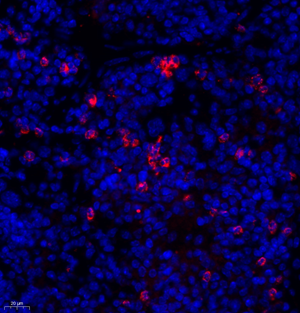

| IF analysis of MPO (GB11224). Sample: Mouse spleen (Paraffin), 4% PFA (G1101) 12-24h. Antigen retrieval: TE buffer (pH 9.0) (G1203),98°C,20min. Blocking buffer: 3% BSA in PBS (GC305010), RT, 30min. Primary antibody: 1: 1200, 4°C overnight. Secondary antibody: Cy3 conjugated Goat Anti-Rabbit IgG (H+L) (GB21303), 1: 300 RT, 1h. |